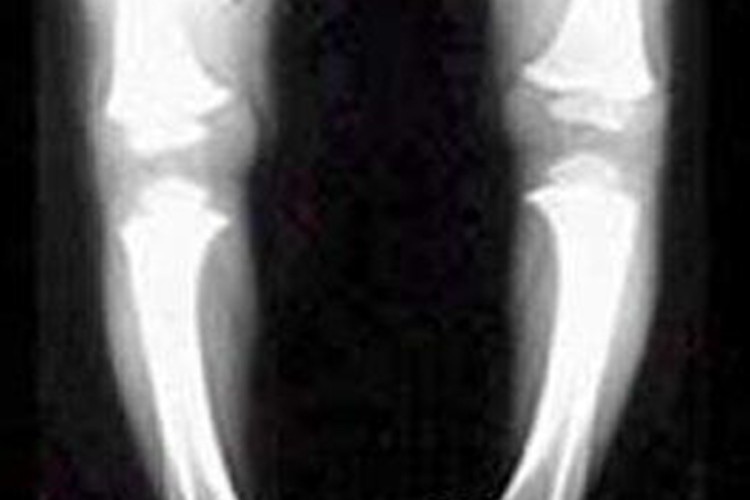

判断宝宝是否O型腿主要通过临床表现,以及X线摄片检查结果明确诊断。

双腿伸直并拢时两膝股骨内侧髁不能接触,若使其接触则小腿必须交叉。双踝靠拢,两膝之间的距离称为踝间距,测量踝间距越大,膝内翻程度越重。自髂前上棘至足1、2趾之间拉一条线,正常时该线通过髌骨正中,若髌骨向外侧偏离中线则视为膝内翻,偏离越远膝内翻越重。此法也可用作双侧内翻程度的比较。

X线摄片:包括股骨下段与胫骨全长的正位片,可明确畸形的部位和有助于测量内翻的角度。畸形多在胫骨上干骺端;若在股骨下干骺端者,则表现为股骨内侧髁发育小而短;也有在胫骨中下段弯曲者;在干骺端者,骨骺线多在凸侧增宽,骨干内侧骨皮质相对增厚;若为佝偻病者,骨骺边缘不清,骺板增厚,临时钙化带模糊,呈毛刷状或杯口状,骨皮质稀疏。